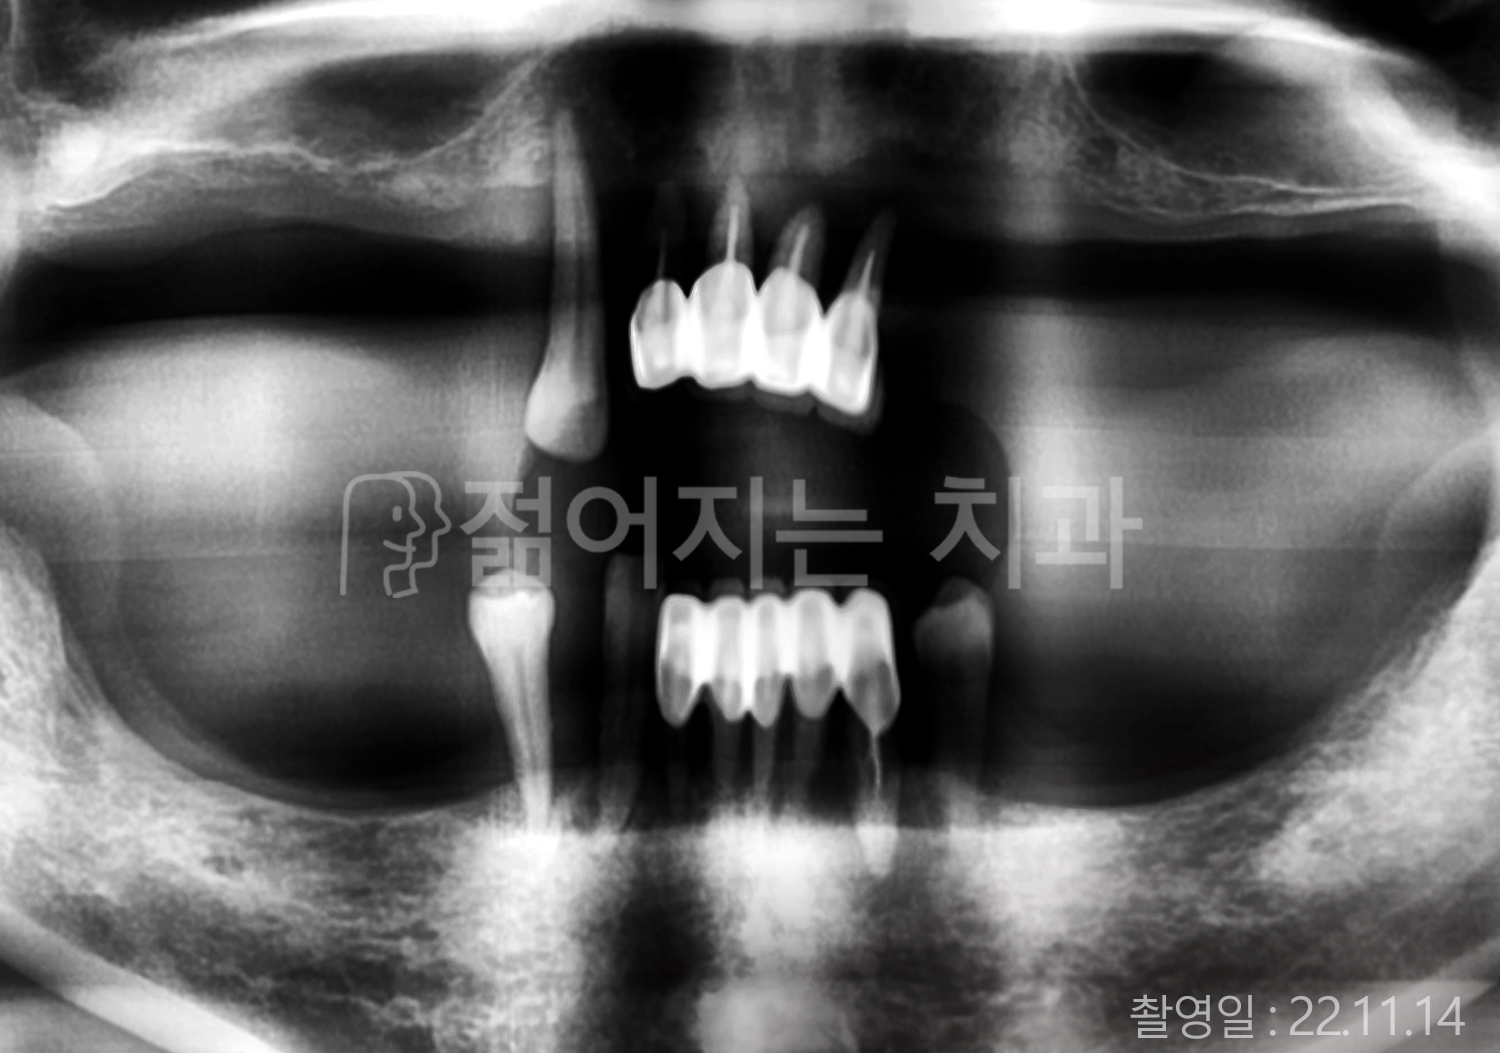

• 50대 고혈압, 당뇨, 고지혈증 전체치아 10개 이상 임플란트

• 50대 고혈압, 당뇨 전체치아 10개 이상 임플란트